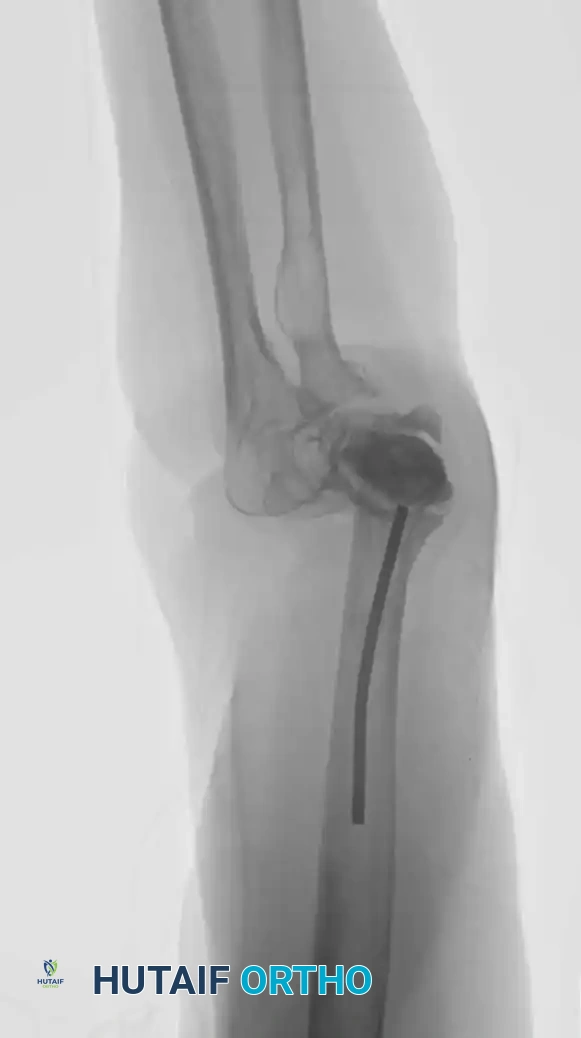

While proximal humeral resections dominate shoulder oncology, tumors extending into the humeral diaphysis or distal humerus require equally complex limb salvage strategies. Total humeral replacement or distal humeral megaprostheses are viable options when the radial nerve can be preserved or grafted.

Intraoperative Imaging and Margin Assessment

Continuous intraoperative assessment using fluoroscopy and frozen section pathology is mandatory. The following images demonstrate various stages of complex upper extremity resections, allograft preparations, and prosthetic implantations across the humerus and elbow joint.